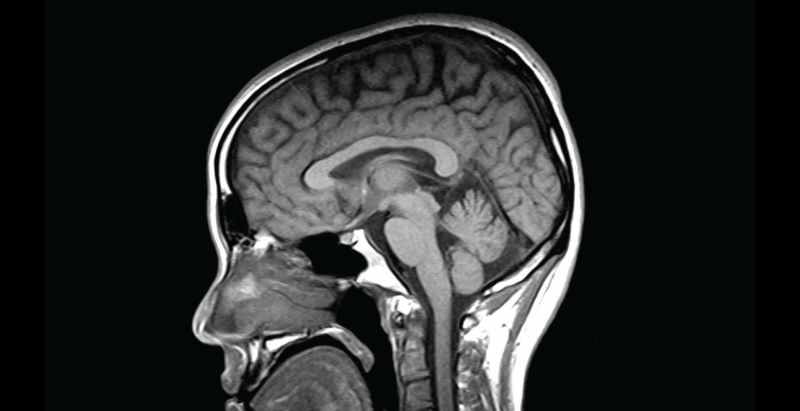

Eventually, Brothers called another Uber that drove her to the ER at Mount Sinai Morningside. There, a brain scan revealed her diagnosis: a ruptured aneurysm. As per The Post, it was the size of a marble and was bleeding into the space surrounding her brain.

“When the aneurysm bleeds, the blood spreads very quickly and causes inflammation throughout the whole brain and in the arteries around the brain,” Kellner told The Post. “That can cause seizures, increased fluid buildup and increased pressure.”